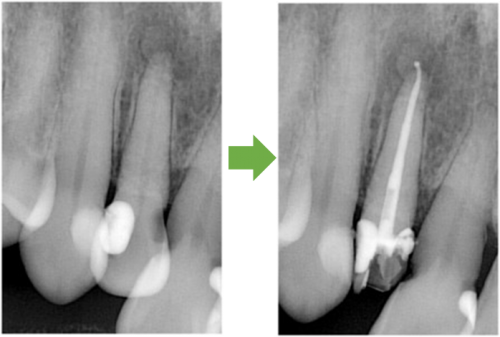

歯髄壊死 右上の前歯 川口の歯科 歯医者 さかえ歯科クリニック

2014年12月16日

術 前 術 後